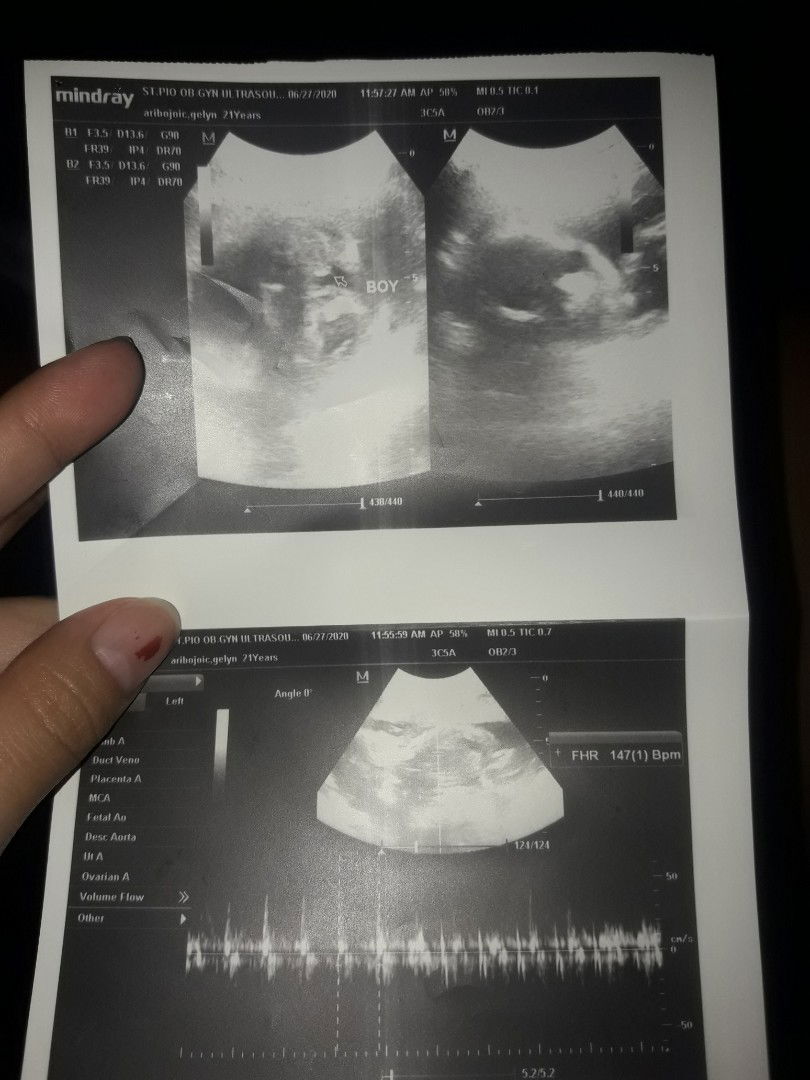

ULTRASOUND

Unexpected and Feeling surprised. First ultrasound Boy daw pero kaka ultrasound ko lang and GIRL naman ngayon. Momshies? What do you think, girl na ba talaga?

Mga mamsh, I'm 21 weeks na po and nag pa ultrasound na din. Medyo malabo po kase yung ultrasound dahil malikot po siya kaya tanong ko lang po kung sure na po ba talaga na boy ang gender ng baby ko?

Mas nakikita po ng OB pag boy ang gender...ipaconfirm nlng pag next check-up.